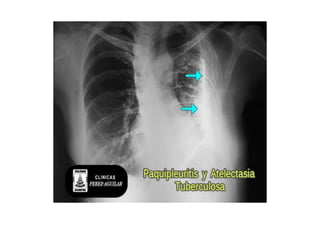

Rx tórax PA . Patrón reticular, atelectasia lobulo superior y

engrosamiento pleural hacia ambos vértices a predominio derecho